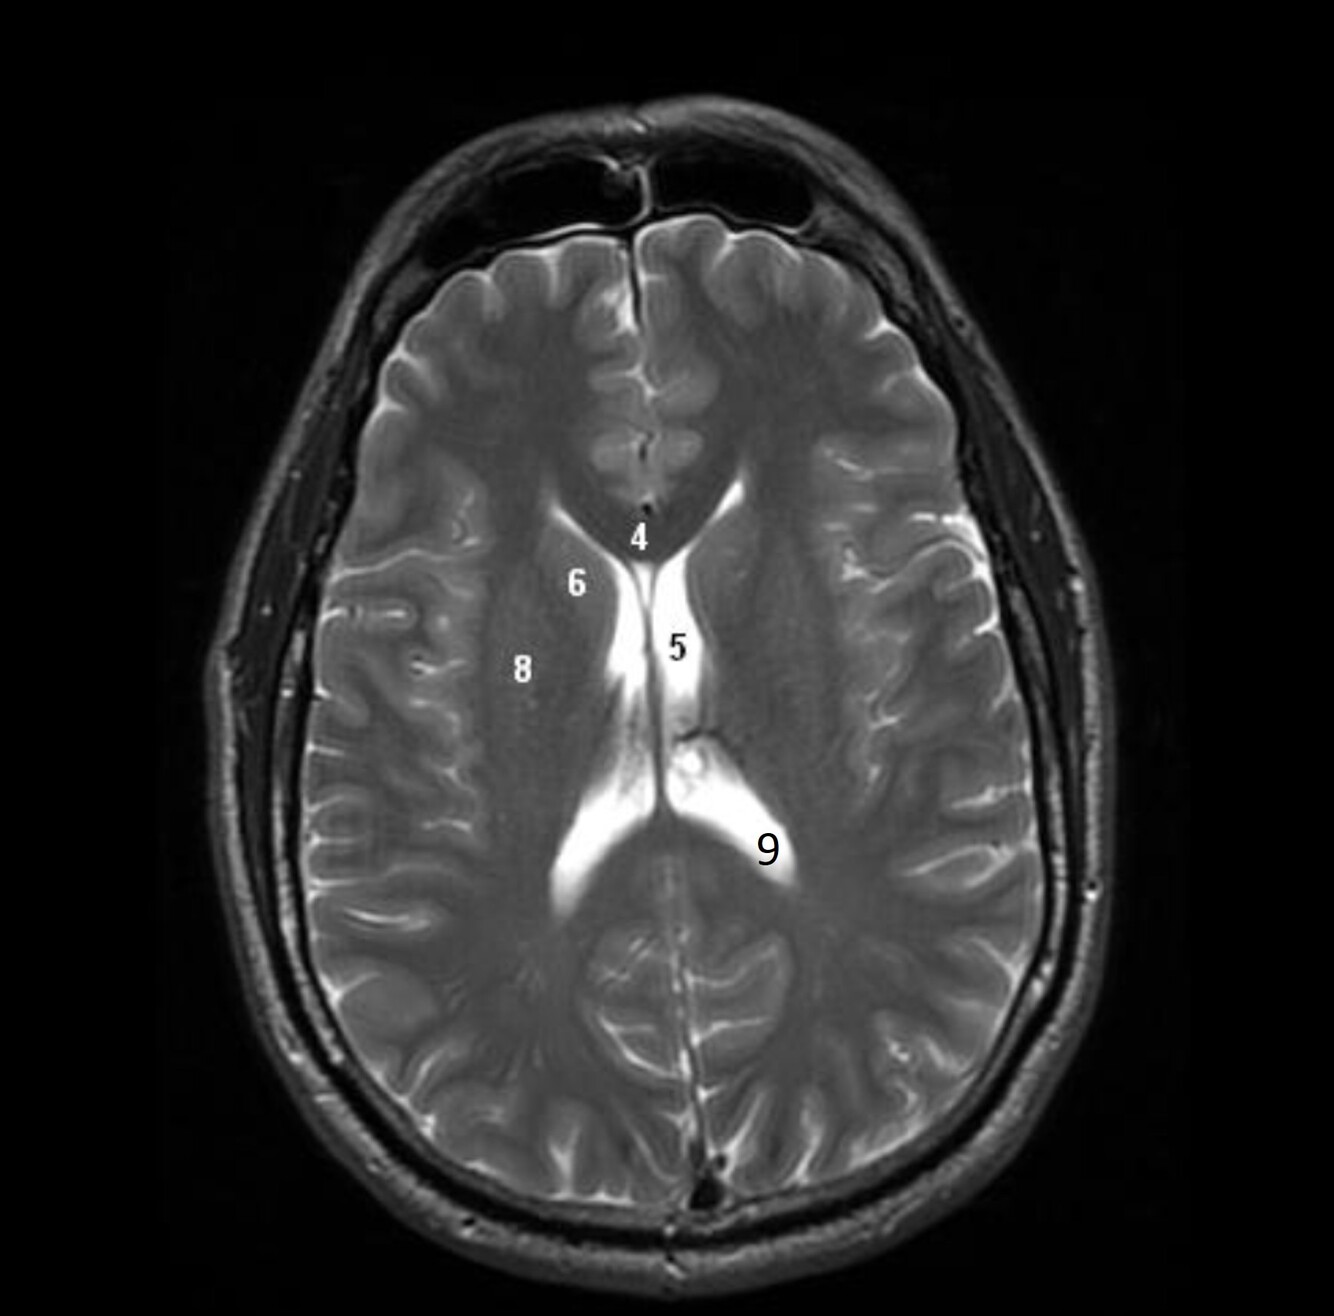

5

Label 2,3,4,5,7,8

A

2=Rt Caudate nucleus

3=Corpus callosum

4=Lt lateral ventricle

5=Third ventricle

7= Septum Pellucidum

8= Rt Interventricular foramen